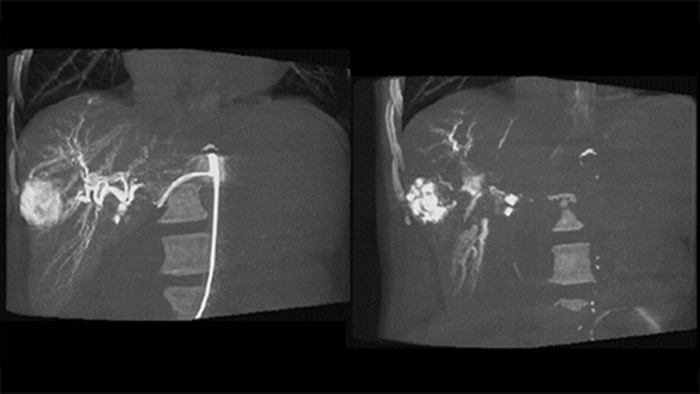

患者の左側のCアーム軌道をずらすことで、CBCT Openでは患者テーブルのオフセンター配置を可能にし、FOVのセンタリングが改善されます³⁻⁴。これにより、画像の収集範囲が拡大し、肝臓周辺の腫瘍の視覚化に役立ちます⁴。

CBCT Dualを使用すると、動脈相の3D画像収集による血管構造と後期動脈相(遅延相)を表示し、造影剤の蓄積状況を一連の操作で視覚化できます。5